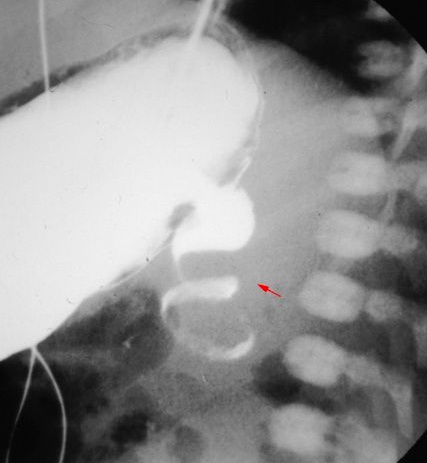

The classic radiographic sign associated with duodenal atresia is the “double bubble” sign on abdominal radiography.

The double bubble is denoted the higher, larger, left-sided stomach bubble together with the lower, smaller, right-sided bubble of the dilated proximal duodenum.